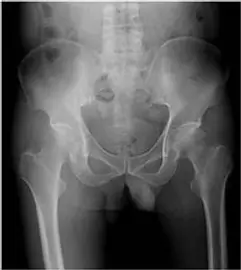

- X光影像 (骨盆正面觀):

- 顯示雙側髖關節。仔細觀察左側股骨頭 (圖片右側),雖然關節間隙 (joint space) 尚稱保留,未見明顯狹窄 (這一點與嚴重退化性關節炎不同),但股骨頭的輪廓可能已出現輕微的不規則或密度變化 (sclerosis),這是 AVN 進展至中期的表現。右側股骨頭則相對圓滑且密度均勻。

- 影像符合:MRI T1WI 上的 "Serpentine line" (蜿蜒線) 或壞死區域的邊界線是 AVN 的典型特徵。X光顯示關節間隙相對保留,排除了原發性關節炎。

- 退化性關節炎 (OA) 的典型 X 光表現包括:關節間隙變窄 (joint space narrowing)、軟骨下骨硬化 (subchondral sclerosis)、骨刺 (osteophytes) 及軟骨下囊腫 (subchondral cysts)。

- 本題影像中,關節間隙並未嚴重變窄,且 MRI 的特徵性壞死邊界線並非 OA 的表現。OA 通常發生在年齡更大的族群,或是作為 AVN 晚期的次發性變化。

患者為中年男性,具備長期酗酒的高風險因子,臨床表現為單側髖部疼痛。MRI T1WI 影像清楚顯示左側股骨頭內有典型的低訊號蜿蜒帶 (serpentine line),界定了壞死區域,這是 Avascular Necrosis (AVN) 的確診性特徵。相比之下,OA 會有關節間隙狹窄,骨肉瘤會有侵襲性骨破壞,嗜伊紅性肉芽腫則好發於兒童且呈溶骨性變化。因此,最可能的診斷為 (A)。

- X-ray:早期可能正常。中期出現 "Crescent sign" (新月徵,代表軟骨下骨折)。晚期股骨頭塌陷 (Collapse)。